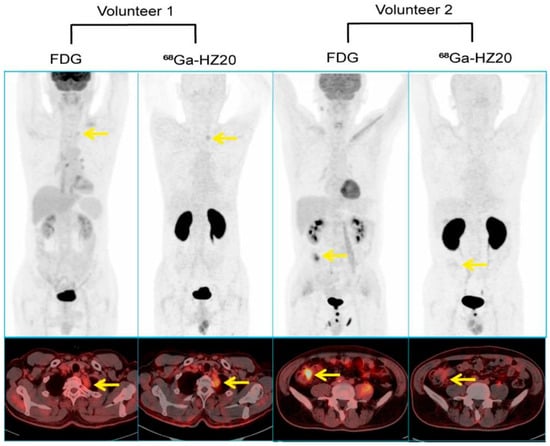

- Zhang, Q.; Liu, T.; Ding, J.; Zhou, N.; Yu, Z.; Ren, Y.; Qin, X.; Du, P.; Yang, Z.; Zhu, H. Evaluation of (68)Ga- and (177)Lu-Labeled HZ20 Angiotensin-Converting Enzyme 2-Targeting Peptides for Tumor-Specific Imaging. Mol. Pharm. 2022, 19, 4149–4156. [Google Scholar] [CrossRef]